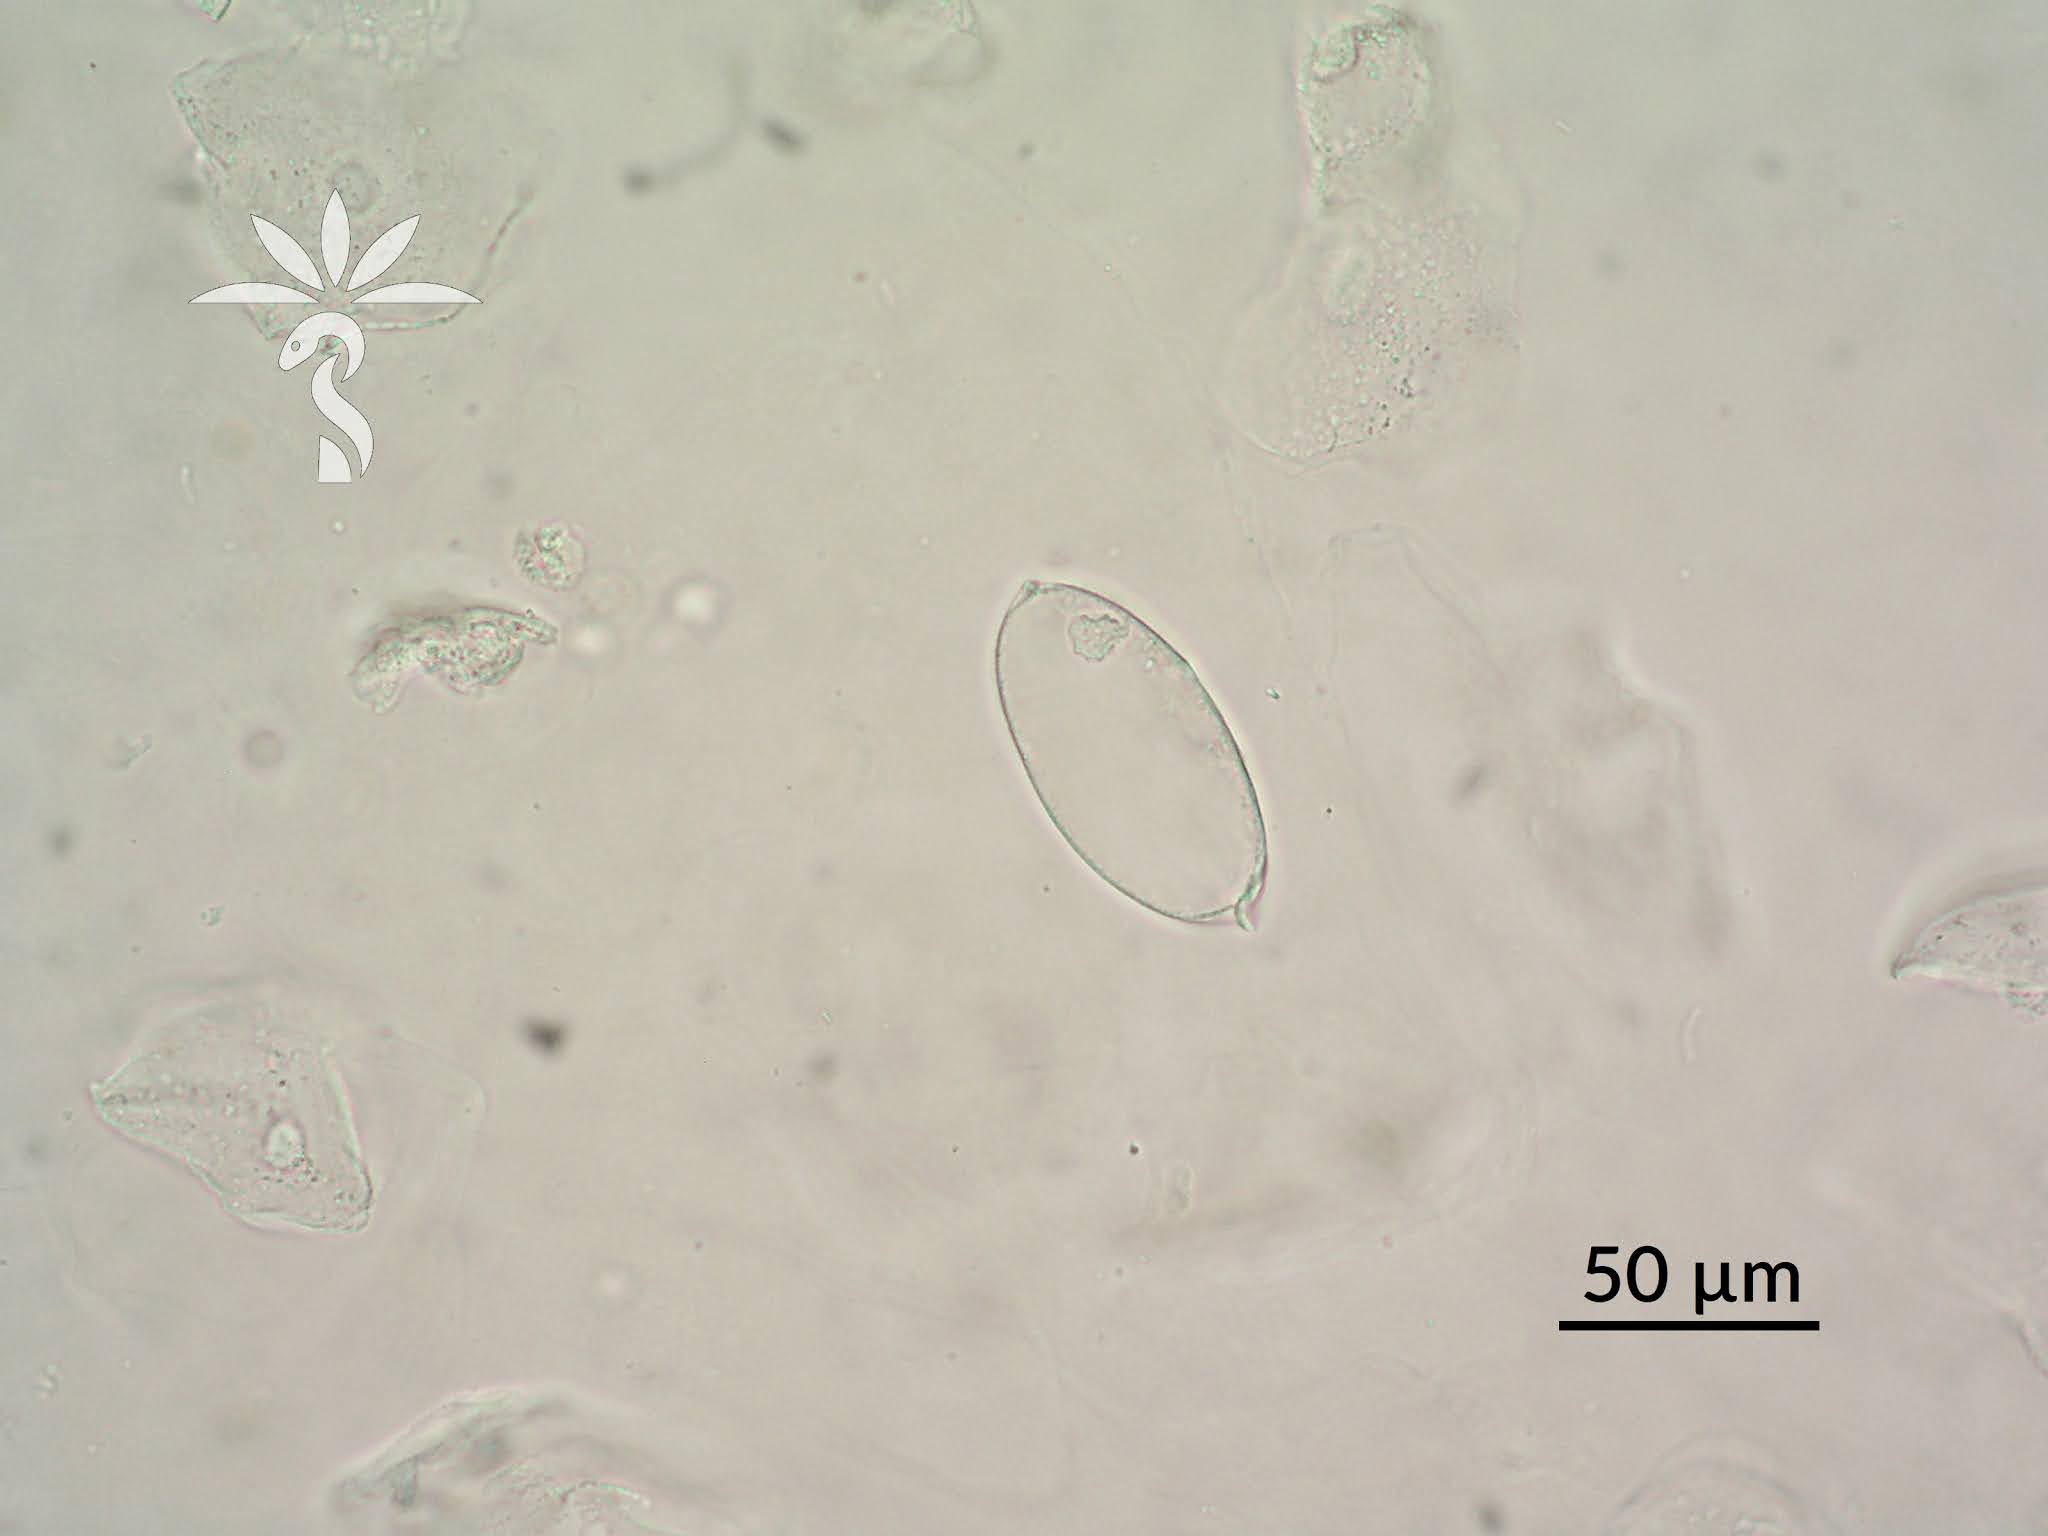

Urinary Tract Infection by Strongyloides stercoralis A Case Report

Schistosoma Haematobium Parasite Ova In Human Urine Specimen Under Amazon Urine Parasite Discover the legend of the candirú that supposedly swims. Its spiny gill covers anchor it under the operculum of the larger. But perhaps the most frightening creature of them. Is a parasite that normally lives in the gills of larger fishes where it feeds on the host's blood. Learn about the candiru, a tiny, parasitic catfish that lives in the. Amazon Urine Parasite.